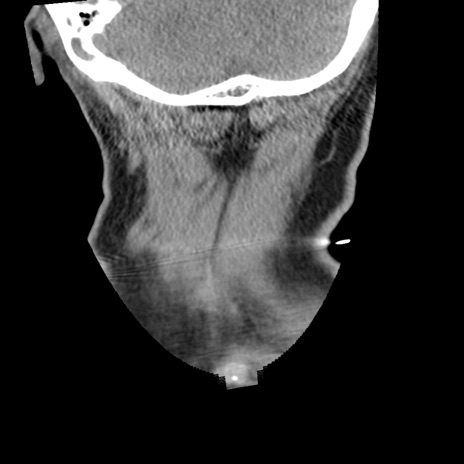

症例50 頚椎CT(冠状断像)

【症例】60歳代女性

【主訴】後頭部〜右後頸部にかけての痛み

【現病歴】本日飲食店でコーヒーを飲んでいたところ、突然後頭部〜右後頸部にかけて痛みが出現し、右上肢の感覚障害を伴ったため救急要請。

【身体所見】脳神経学的に明らかな異常所見を認めず。右上肢に軽度の感覚障害あり。

異常所見と診断は?